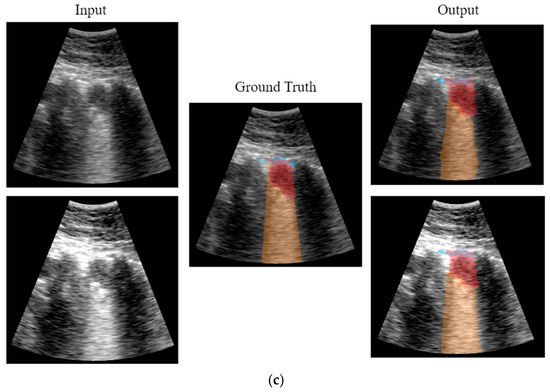

CNN Output

3.2. Real-Time Implementation Results